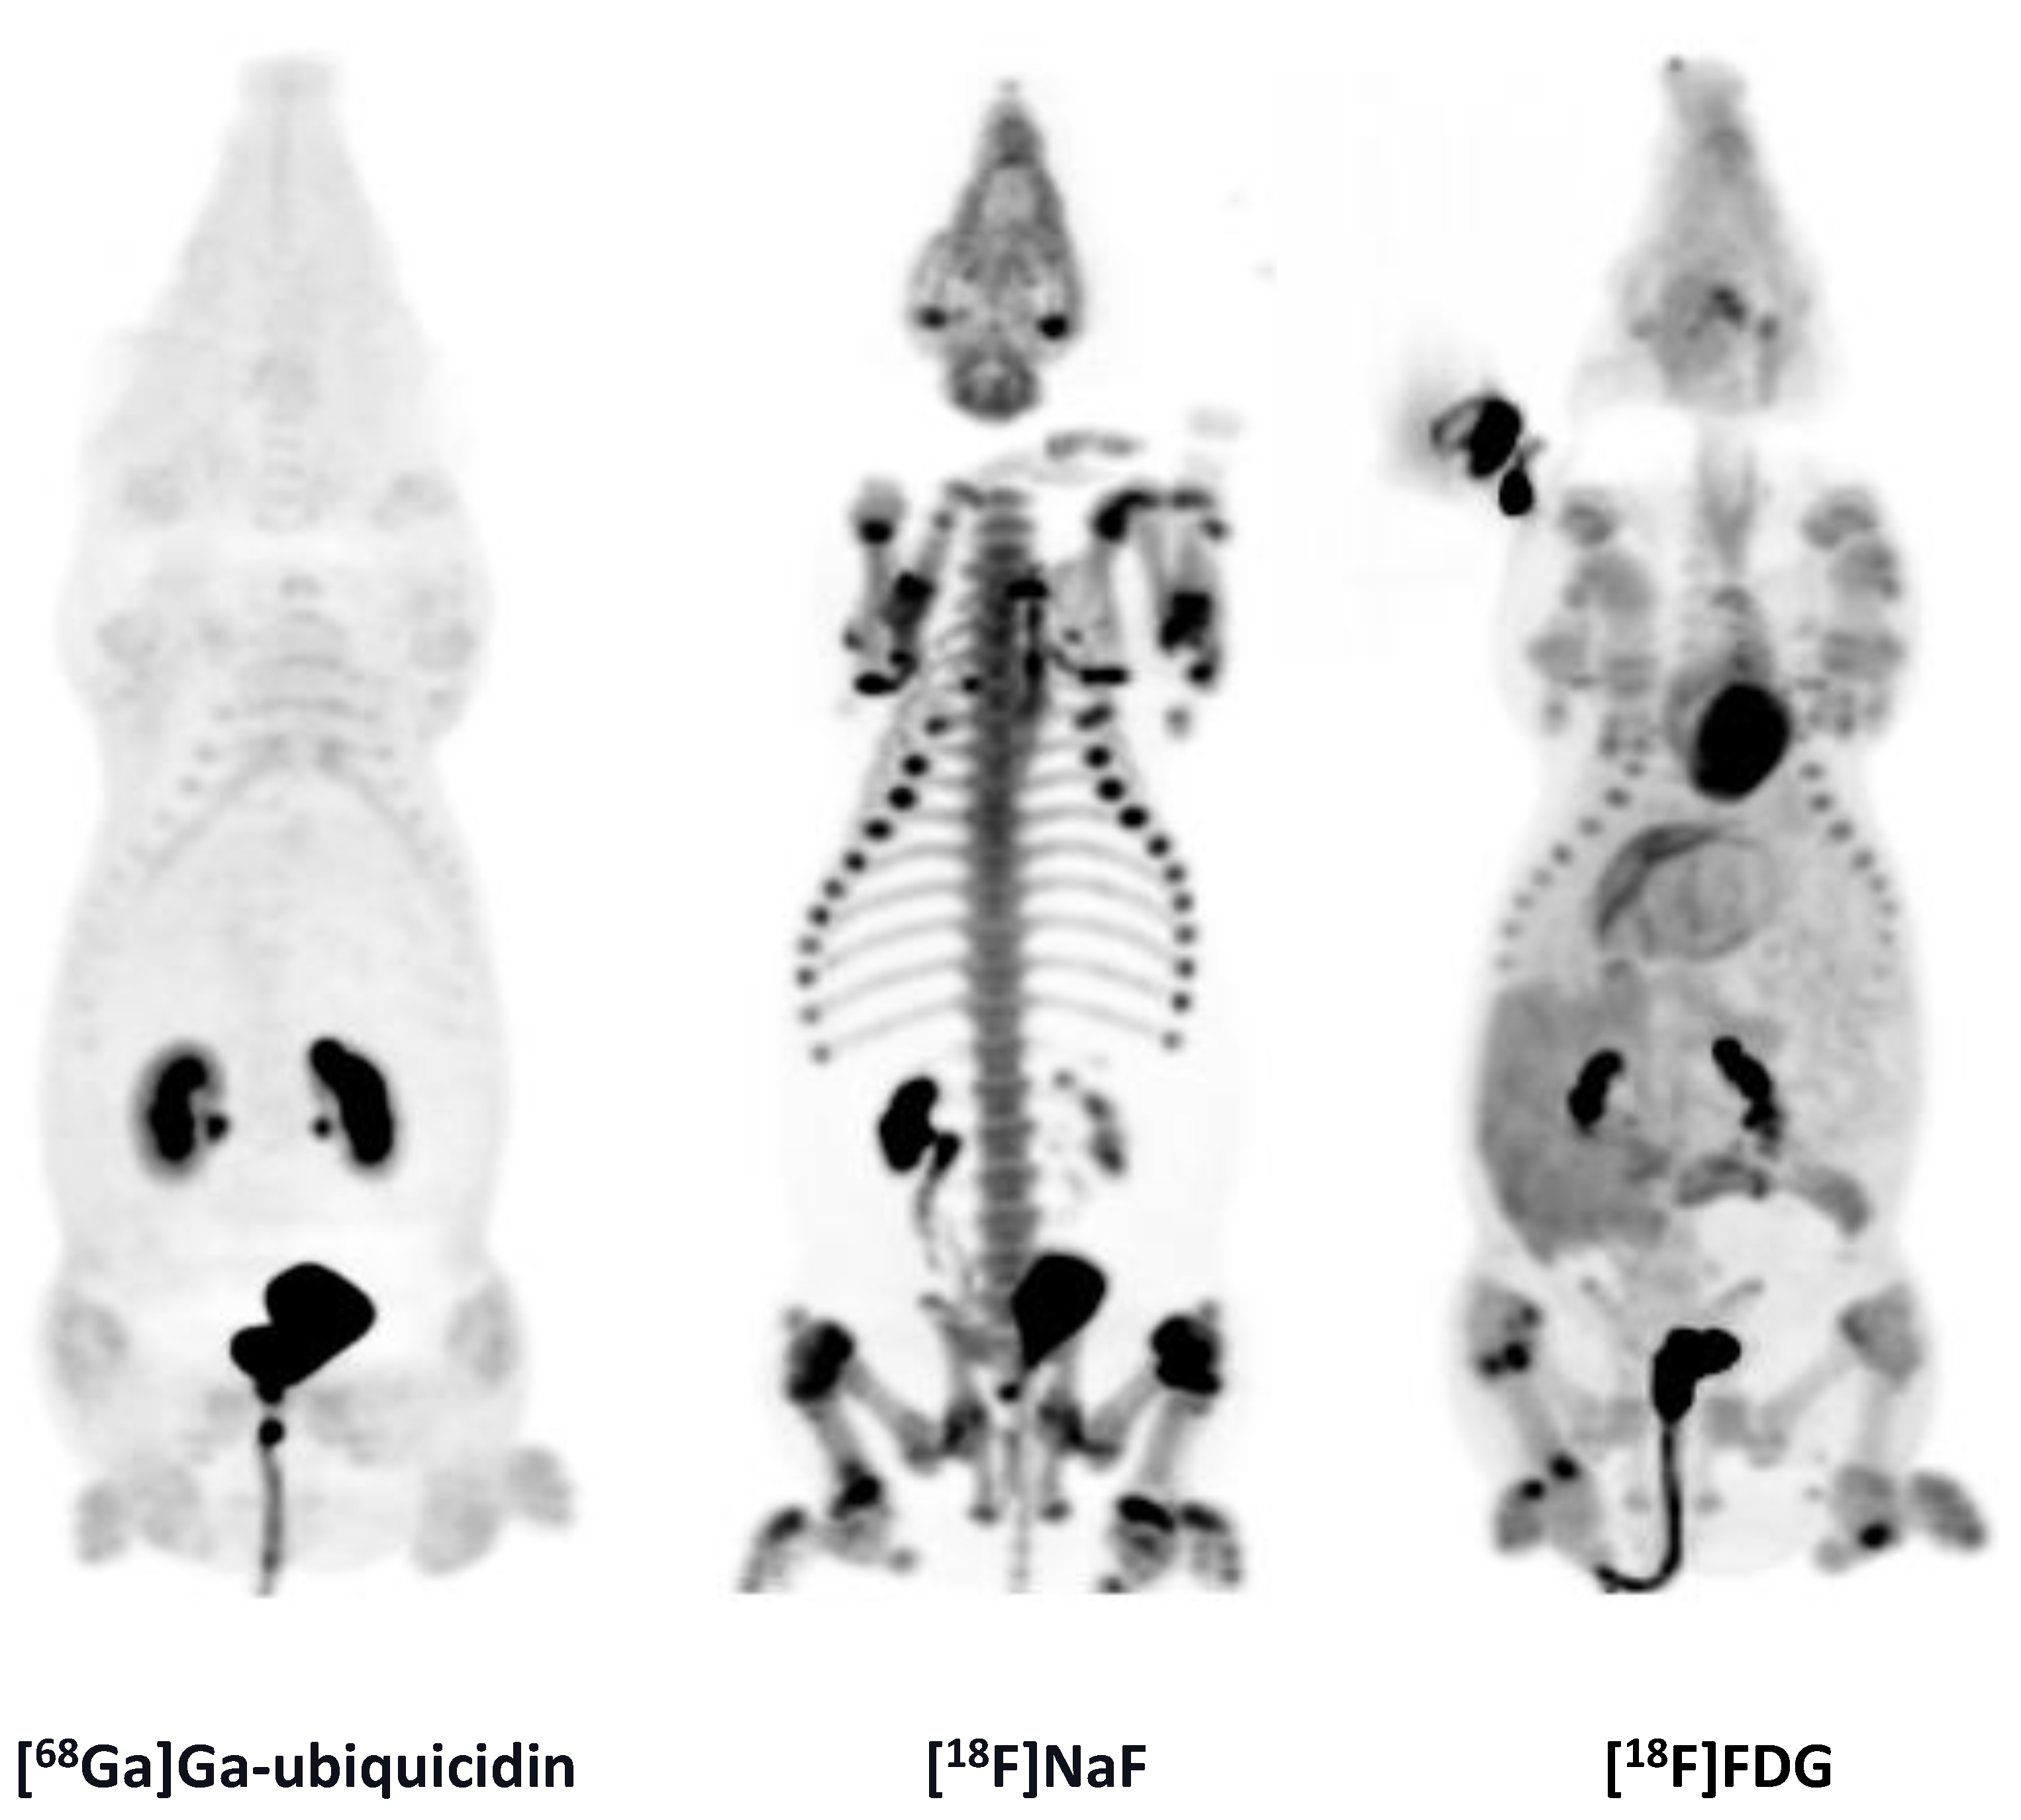

While previous evaluation in murine subcutaneous S. aureus infections showed uptake of [68Ga]Ga-DOTA-K-A9 [9,14], we saw no increased tracer activity of the two S. aureus phage displayed selected peptides, [68Ga]Ga-DOTA-K-A9 (Figure 1) and [68Ga]Ga-GSG-KA-11 (Figure 2) in 9 and 5, respectively, porcine OM lesions. Figure 3 shows the bio-distribution of the peptides in pigs. Both peptides were excreted by the liver and kidneys.

MIPs of the [18F]FDG, [68Ga]Ga-DOTA-K-A9, and [68Ga]Ga-DOTA-GSGK-A11.

CT images of two OM in the distal right femur in pig 9 in the axial view. [68Ga]Ga-ubiquicidin and [18F]NaF compared to [18F]FDG accumulation in the same lesions. Comparable SUV scales are shown to the right of the PET images. For a demonstration of the uptake of [18F]NaF in the growth zones of long bones, a wider SUV-scale is used in the last picture. The CT image shows sequester formations and lysis of the cortical bones.

2.3. [18F]NaF

We saw no accumulation of [18F]NaF in 15 OM lesions (Figure 4). [18F]NaF was distributed to the growth zones of the bones (Figure 4) and excreted by the kidneys (Figure 5).

2.4. [68Ga]Ga-Ubiquicidin

We saw no accumulation of [68Ga]Ga-ubiquicidin in 12 OM lesions. [68Ga]Ga-ubiquicidin was excreted by the kidneys (Figure 5).

MIPs of the [68Ga]Ga-ubiquicidin, [18F]NaF, and [18F]FDG distribution in pig 9.